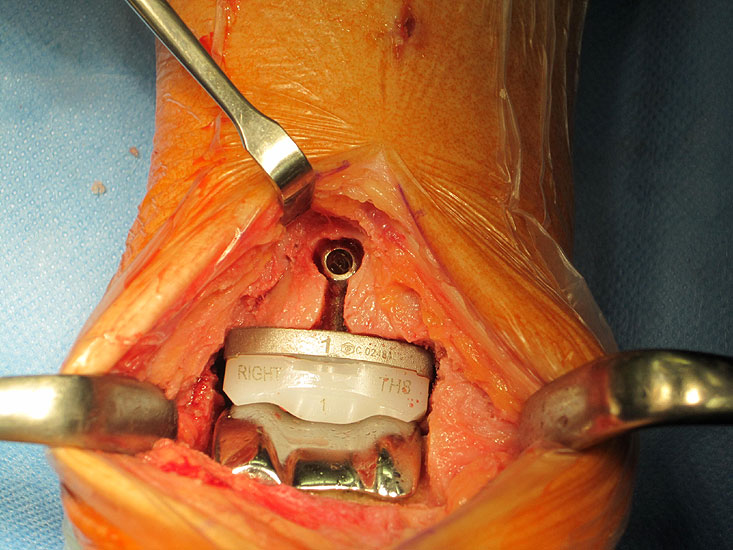

Das Operationsprinzip umfasst eine minimale Knochenresektion mit zementfreier Implantation der Prothesenkomponenten am oberen Sprunggelenk.

Voraussetzungen für eine langfristige stabile knöcherne Verankerung der Komponenten sind eine möglichst große Kontaktfläche zwischen Implantat und Knochen in der subchondralen Zone sowie die Vermeidung der Schwächung der kraftübertragenden Anteile der distalen Tibia. Dies betrifft insbesondere die ventrale Kortikalis der Tibia (Hintermann 2005).

• Prothesenplanung anhand von Röntgenschablonen (Abb. 1 und 2).